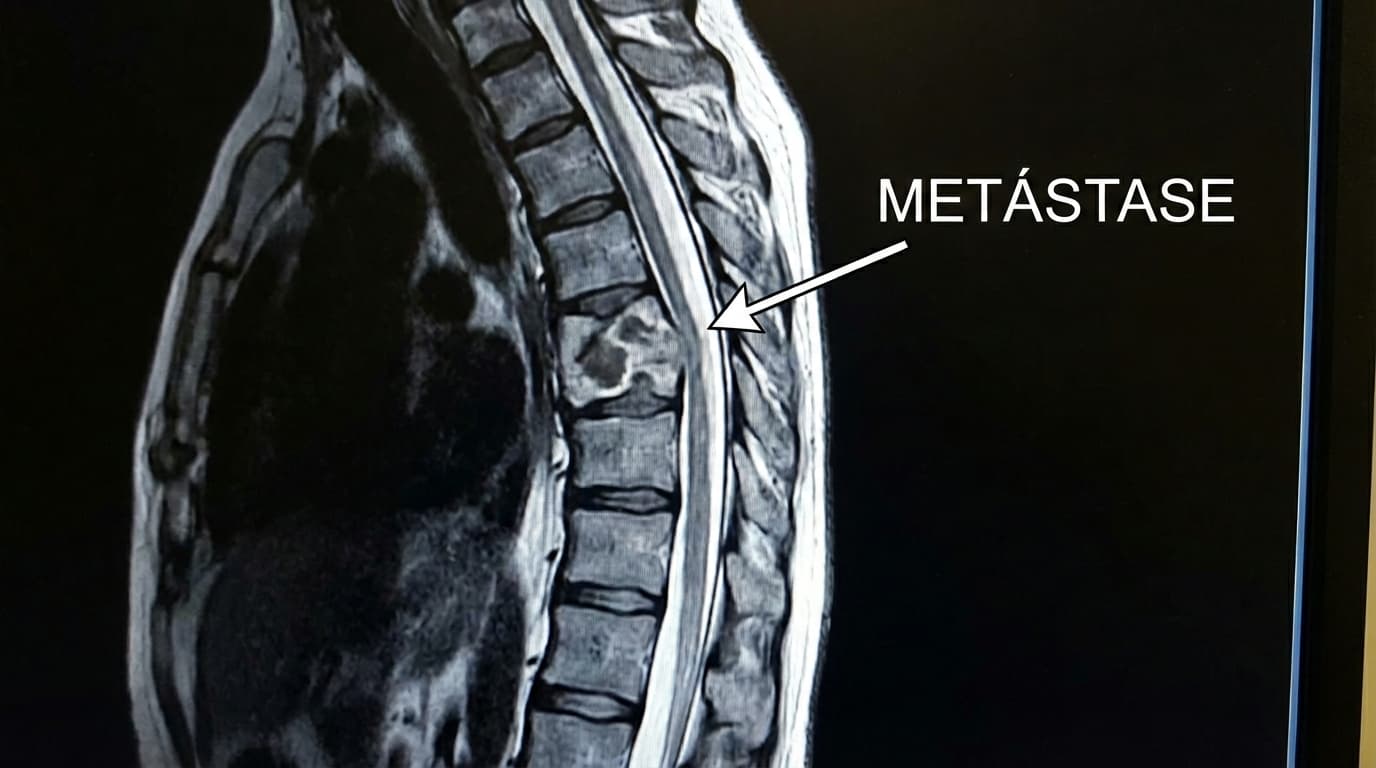

Dor causada por metástases (câncer que veio de outro lugar — mama, próstata, pulmão, rim, mieloma) ou tumores primários da coluna. O tumor destrói o osso vertebral (fratura patológica), comprime raízes nervosas (ciática) ou esmaga a medula (paralisia iminente).